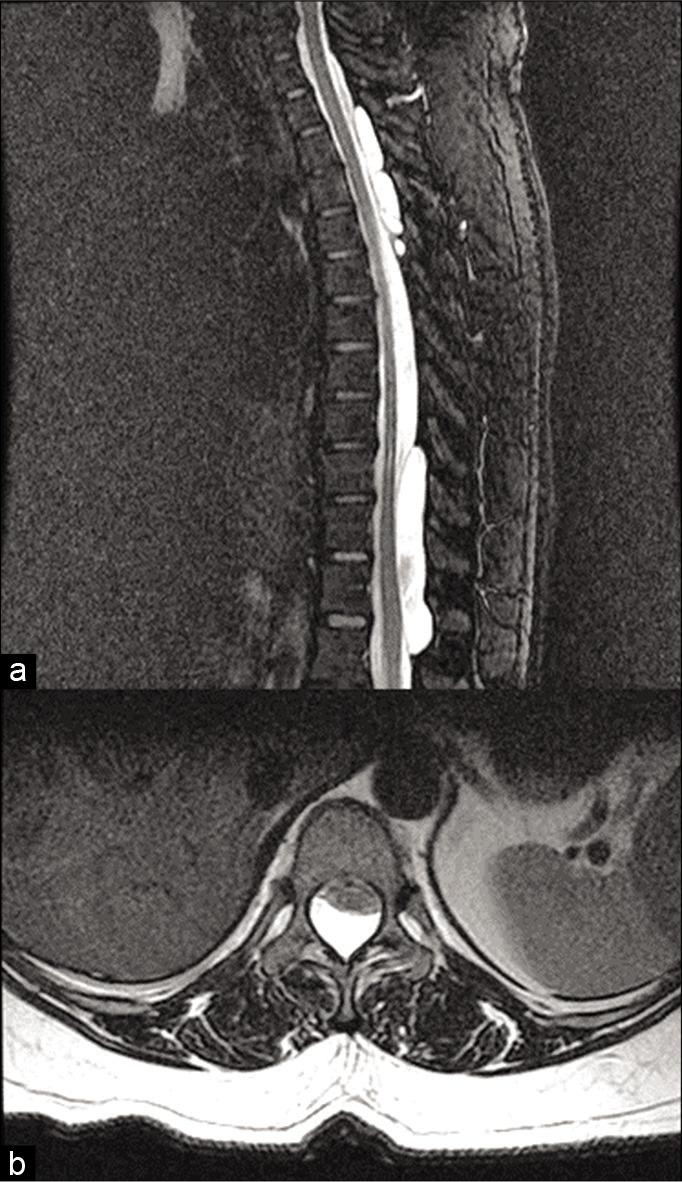

A 38-year-old female presented with a history of two episodes of falling due to transient weakness in the lower limbs. The neurological examination showed normal motor and sensory function, but hyperreflexia. The thoracic magnetic resonance imaging revealed multiple extradural SACs between the T3-L1 levels. Following complete surgical resection of the most symptomatic cyst, she did well. The histopathological examination confirmed a Type I extradural SAC.

一名38岁女性有两次因下肢短暂无力而跌倒的病史。神经系统检查显示运动和感觉功能正常,但存在反射亢进。胸椎磁共振成像显示T3-L1水平之间有多个硬脊膜外SACs。在对最有症状的囊肿进行完全手术切除后,她恢复良好。组织病理学检查证实为I型硬脊膜外SAC。